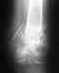

По механизму травмы похоже на частичное повреждение связок. Лечат Вас оптимально - надо создать неподвижность в суставе на несколько недель, чтобы поврежденные ткани могли срастись. После прекращения иммобилизации шиной надо будет разработать движения, восстановить функцию мышц. Потом вернуться к привычной физической активности. Если проявятся какие-то проблемы - тогда уже их и оценивать "с чистого листа".